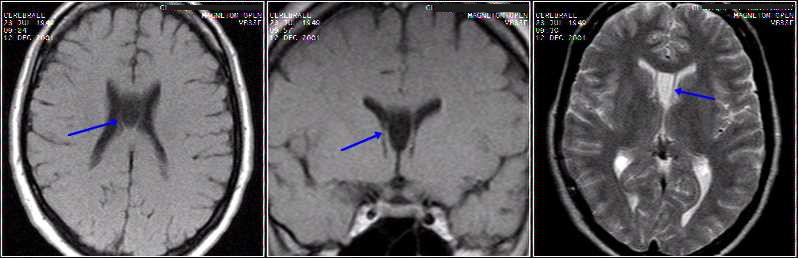

IMAGE DU MOIS - CASE OF THE

MONTH

Brain sag. FLAIR, cor. T1 Gd,

axial T1 Gd & T2: cerebellum hemangioblastoma.